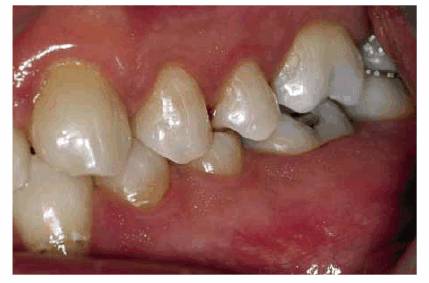

patient (Figures 17-1A to

C

Figure 17-1A to C: These photographs illustrate the complex dental condition of a 71-year-old male: (A) The palatal cervical regions of the maxillary anterior teeth exhibit sharp, wedge-like lesions that are characteristic of abfraction. These areas would be difficult, if not impossible, to have resulted from toothbrush abrasion. (B) The buccal aspects of the maxillary posterior teeth show smooth, concave configurations that are consistent with toothbrush abrasion and/or erosion. (C) The buccal surfaces of the mandibular teeth have lesions that possess components of both abfraction (sharp margins in the occlusal regions) and abrasion (concave geometry and gingival recession in the cervical regions).